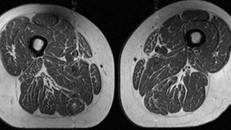

Ảnh minh họa